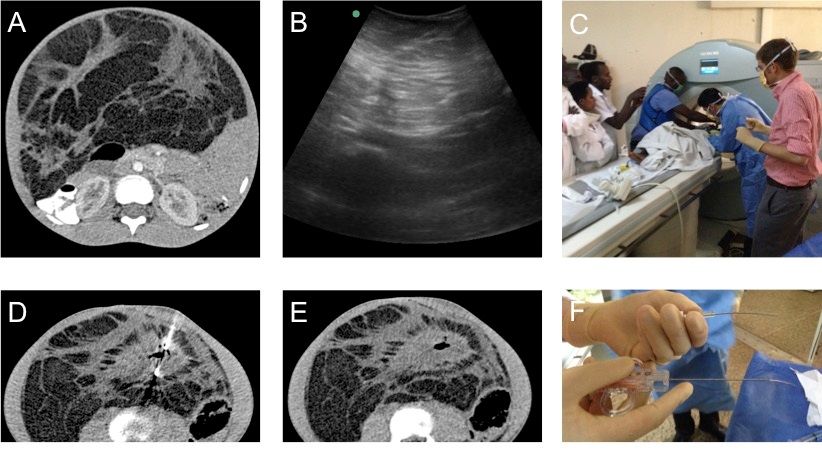

A: Pre-procedural computed tomography image demonstrating a predominately fat containing abdominal mass with several scattered islands of soft tissue concerning for liposarcoma.

B: Pre-procedural ultrasound image showing the ill defined infiltrating nature of the mass. Given an inability to adequately differentiate the soft tissue components under ultrasound, computed-tomography-guided biopsy was completed.

C: Intra-procedural photograph showing the setup and placement of the introducer needle in the first ever computed tomography-guided biopsy completed in Rwanda.

D: Intra-procedural computed tomography image demonstrating placement of the biopsy device within the soft tissue component.

E: Post-procedural computed tomography image demonstrating air within the soft tissue component confirming that the soft tissue component was indeed biopsied.

F: Photograph showing significant bending of the needles due to the hard nature of the mass raising the suspicion for a fibrous tumor such as a desmoid.